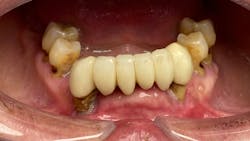

The signs and symptoms of addiction are well-known and include rampant caries (figure 1), especially smooth surface and anterior interproximal lesions, fractured teeth from bruxism and clenching, and gum disease from oral hygiene neglect.5 The acidic nature of these drugs combined with the xerostomia they cause can create unexplained and rapid deterioration of teeth, which is one of the hallmarks of drug use.